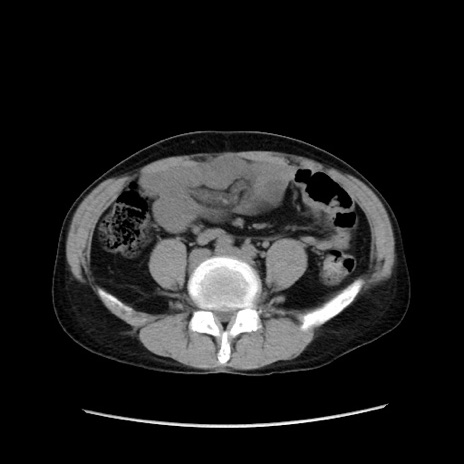

症例37(横断像)

【症例】40歳代 男性

【主訴】腹痛

【現病歴】4時間ほど前に電車に乗車中に臍部上より腹痛出現。徐々に増悪し起立困難となり、救急外来受診。生ものは数日食べていない。今朝お雑煮を食べた。

【身体所見】BT 36.8℃、BP 117/84mmHg、HR 91/min、SpO2 97%、苦悶様、腹部:臍上部広範囲圧痛あり、反跳痛±

【データ】WBC 8100、CRP 0.03